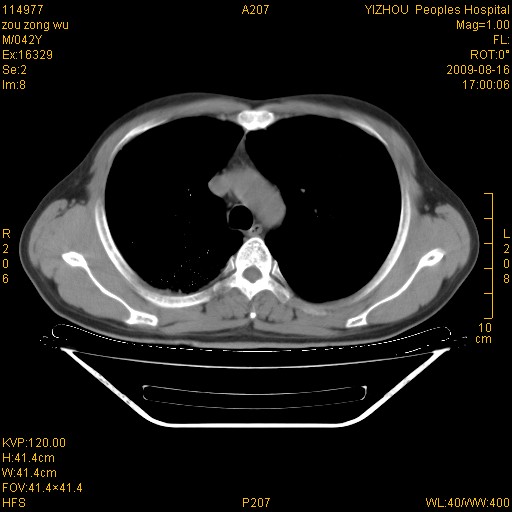

以下是引用zjzjr在2009-8-17 10:42:00的发言:[br]右侧间质性肺炎伴纤维化,右肺下叶肺囊肿伴感染(不除外外伤后引起),右肺野及胸壁软组织\\肝内见多发斑点状,中枪了吧.右侧胸膜肥厚\\粘连.